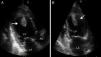

Case reportA 27-year-old primigravida woman presented in the emergency room seven days after an uncomplicated spontaneous vaginal delivery. She complained of recurrent temporary speech disturbance and visual impairment twice within six hours. The pregnancy was uneventful and her medical history was insignificant. On physical examination, blood pressure was 110/65 mmHg with a regular heart rate of 105 bpm. Bilateral grade 1–2 pitting pedal edema was present. Carotid auscultation and fundoscopic evaluation were normal. Chest auscultation showed bibasal crackling rales less than one-half way up the posterior lung fields and an apical III/VI systolic murmur with S3 gallop. The electrocardiogram showed normal sinus rhythm. The chest X-ray on admission showed cardiomegaly and pulmonary edema with bilateral pleural effusion. Urgent neurologic investigation with computed brain tomography revealed no evidence of ischemia (Figure 1). The patient was diagnosed with transient ischemic attack. Laboratory tests, including coagulation studies with platelets, D-dimers, prothrombin time and activated partial thromboplastin time, were within the normal range except for BNP, which was elevated (1300 pg/ml; normal <100 pg/ml) and C-reactive protein (0.30 mg/dl; normal <0.5). The thyroid hormone profile was normal. Transthoracic echocardiography (TTE) showed global left ventricular hypokinesia, left ventricular end-diastolic dimension of 65 mm with an ejection fraction of 22% (by Simpson's method) and moderate mitral regurgitation. A large mobile mural thrombus was observed in the left ventricular apex (Figure 2A and B). Screening for thrombophilia including antithrombin III, protein C and S, plasminogen, fibrinogen and homocysteine levels was normal and antiphospholipid antibodies, β2-glycoprotein I and anticardiolipin antibodies IgG and IgM were negative. Factor V Leiden, prothrombin 20210A polymorphism and MTHFR mutations were not found. The patient was immediately started on intravenous anticoagulation with low molecular weight heparin as well as angiotensin-converting enzyme inhibitors, diuretics and digoxin. A beta blocker (carvedilol) was added after signs and symptoms of congestive heart failure improved. By one month of follow up she had responded well to medical therapy and was asymptomatic; repeat TTE showed no evidence of thrombi in the left ventricle and ejection fraction had improved to 38%.